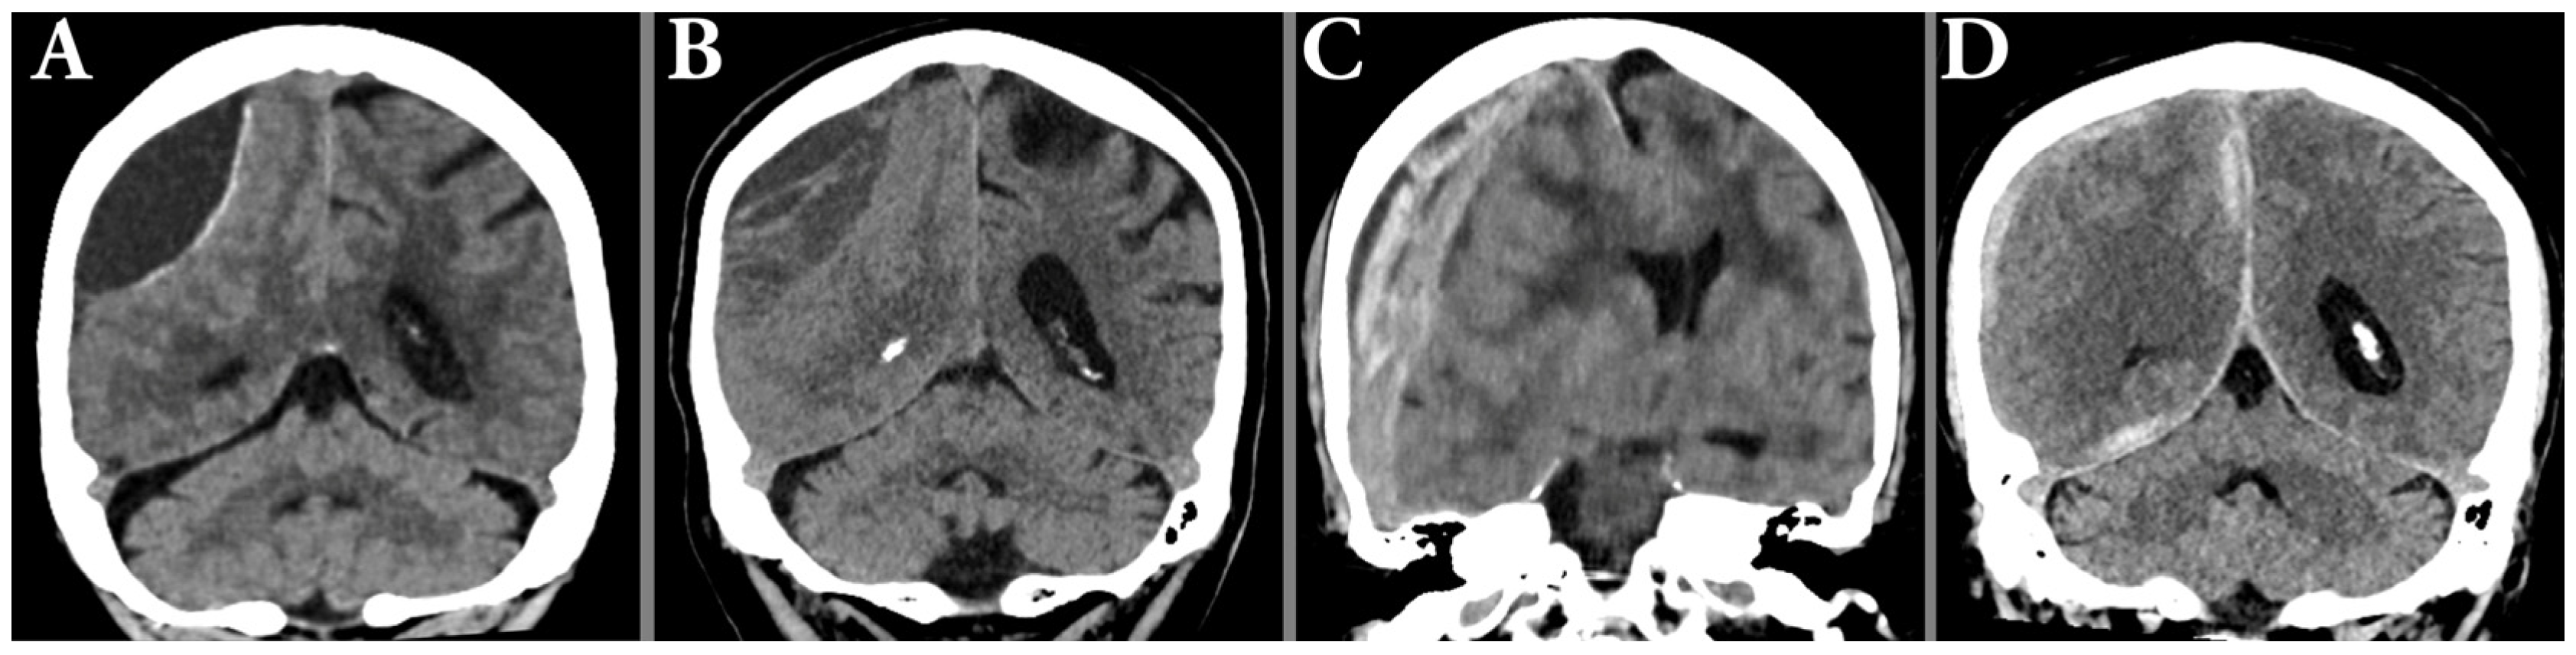

2.8. Hematoma Characterization

2.9. Uni- and Bilateral Hematomas